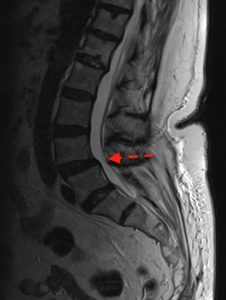

La espondilolistesis es un término médico que define un desplazamiento de las vértebras, habitualmente en el plano sagital (Rx de perfil). También puede verse asociada a escoliosis en el plano coronal (RX AP).

La espondilolistesis en L5-S1 suele venir asociada a una distribución de cargas anómala en ese nivel, por lo que en no pocas ocasiones se asocia a una espondilolisis de la pars (fractura por estrés), escoliosis y/o sacral slope alto.

En función del grado de desplazamiento de las vértebras implicadas se clasifica (Meyerding) en grado I (<25% de la longitud sagital vértebra), grado II (25-50%), grado III (50-75%), grado IV (75-100%) o grado V o ptosis (>100%).